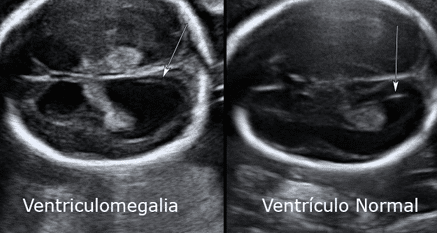

Ventriculomegalia fetal leve: diagnóstico, avaliação e conduta

A ventriculomegalia é definida como a dilatação dos ventrículos cerebrais fetais e é um achado relativamente comum na…